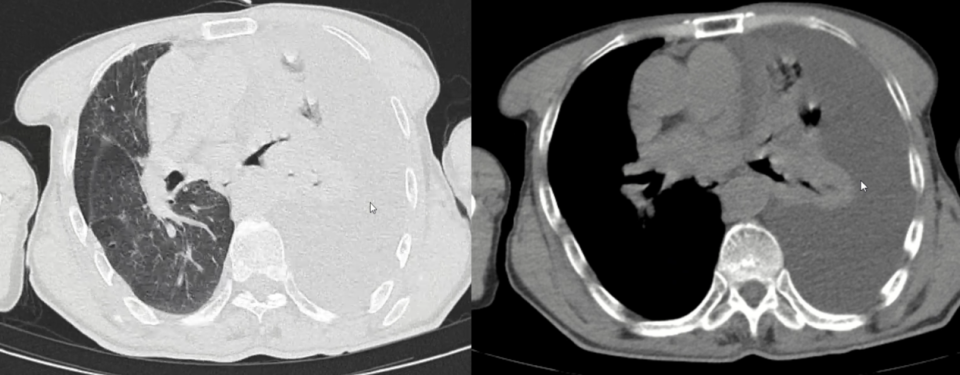

经过进一步病史询问和查体,并未找到白塞病的依据。根据上述科室建议,我们进一步完善PET/CT,检查结果回报:左锁骨区、纵隔、两肺门多发淋巴结糖代谢增高,考虑炎性增生可能;余纵隔、肺动脉区均未见高摄取(图5)。

图5:PET/CT显示纵隔多发淋巴结高摄取